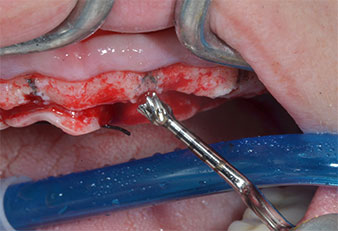

Implant motor (Implantmed)

Fig. 5: The final diameter is achieved with the Piezomed I3A/I3P instruments. For the 10-mm implants at positions 11 and 21 sites are finalized with a 3.5 mm rotary drill in an implant motor (Implantmed).

Due to the relatively hard bone (D2) in this area, the 10 mm long implant sites at positions 11 and 21 were finalized with a 4 mm diameter rotary drill, in combination with a W&H WS-75 L surgical contra-angle handpiece, the W&H Implantmed implant motor and the optional W&H Osstell ISQ module. In contrast, due to the soft bone the posterior sites were prepared to a final 3 mm diameter using the Piezomed I3P instrument. The implants were finally placed transgingivally to osseointegrate for three months (Figs. 6-10). The existing denture was retained on four provisional implants (Fig. 8).